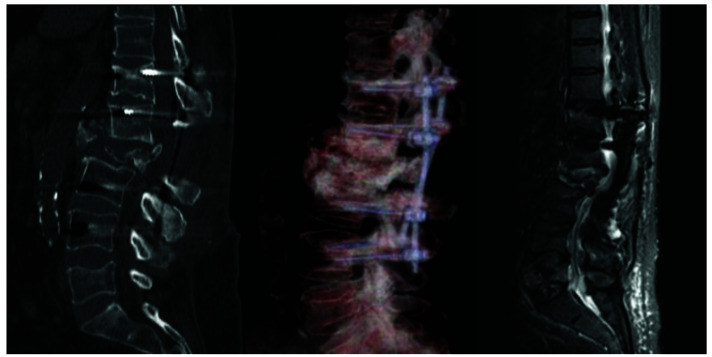

Stabilization of spine using transpedicular screws is the most commonly used instrumentation technique among spinal surgeons. The 'free hand' technique is considered relatively safe and can be performed under x-ray control. Vascular injuries with misplaced screws are rare but potentially fatal complications. Injury of thoracoabdominal aorta by malpositioned screw demands a multidisciplinary approach. Injury of vessel wall might demand screw removal and vessel wall repair. Here we present a case of 72-year-old female patient who underwent long segment fixation of thoracolumbar spine. During follow up, computed tomography (CT) scan and afterwards aortography showed a lesion of the posterior aortic wall by malpositioned screw without signs of bleeding. After meticulous preparation, combined endovascular repair with stent-graft and removal of the penetrating screw were performed. Endovascular treatment was performed simultaneously with screw removal. During screw removal, the patient was in lateral decubital position. The patient was discharged on postoperative day 8. Follow up CT aortography 6 months later showed no leak or other changes in the aorta. We found combined endovascular vessel repair with simultaneous screw removal safe and sufficient for this kind of aortic injury. Although lateral decubital position bears limitations, it gives enough space for the operator. Performing intraoperative aortography provides good insight into stent position and possible bleeding after screw removal.

Abstract Image